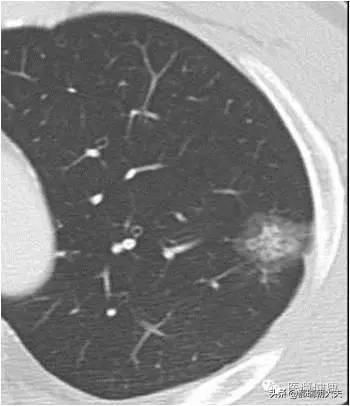

健康診断への意識が高まるにつれ、肺結節が発見される人が増えている。肺結節とは画像診断の用語で、肺結節の画像上の定義は、肺実質に完全に囲まれた、境界明瞭な小さな病変(直径≤30mm).結節の形態は、固結または亜固結に分類される。亜固結はさらに、純粋なすりガラス結節と部分的な固結に分類される。直径30mmを超える病変は結節ではなく腫瘤であり、悪性の可能性が高い。

結節の直径は悪性腫瘍の独立した予測因子であることが研究で示されている。結節の直径が大きいほど悪性腫瘍のリスクは高く、以下の確率がある:結節の直径<5mm:<1%;结节直径为5-9mm:2%-6%;结节直径为8-20mm:18%;结节直径>20mm:>50%。